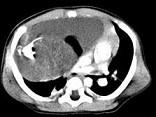

问题 男,28岁,胸闷、右肺呼吸音减弱,请结合影像图像,选择最可能的诊断 ( )

选项 A.畸胎瘤 B.胸腺瘤 C.肺癌 D.先天性囊性腺瘤样畸形 E.支气管囊肿

答案 A